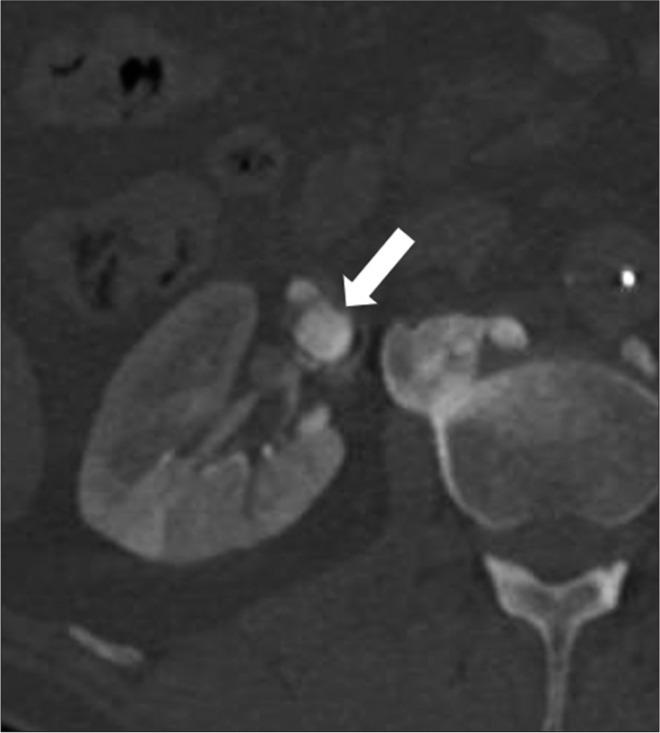

Advances in endovascular approaches have resulted in increasing utilization of minimally invasive techniques to treat visceral artery aneurysms including renal artery aneurysms (RAAs), with high rates of success. The basic endovascular approach to treating RAAs includes stent graft exclusion or coil embolization. Treatment of RAAs with wide necks or at the bifurcation of the main vessel is facilitated by scaffolding techniques, which have been previously described. These techniques have their limitations and cannot be used in all situations. We describe a scaffolding technique using the Comaneci device (Rapid Medical, Israel), a retrievable mesh device meant for intracranial treatment of wide neck or bifurcation aneurysms that we used to safely and successfully treat a 2 cm RAA.

血管内治疗方法的进展使得包括肾动脉动脉瘤(RAA)在内的内脏动脉瘤的微创技术使用率不断提高,成功率很高。治疗RAA的基本血管内方法包括支架移植物置入术或弹簧圈栓塞术。先前已描述过的支架技术有助于治疗颈部较宽或位于主血管分叉处的RAA。这些技术有其局限性,并非适用于所有情况。我们描述了一种使用科马内奇装置(以色列快速医疗公司)的支架技术,该装置是一种可回收的网状装置,用于颅内宽颈或分叉动脉瘤的治疗,我们用它安全、成功地治疗了一例2厘米的RAA。